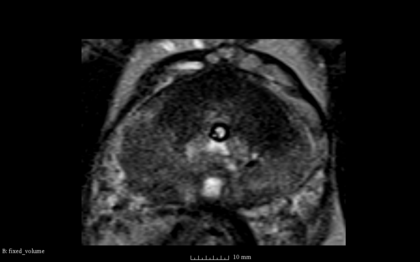

- the following images are shown from left to right:

- [1] Fixed Volume as Reference [2] SimpleITK result after Initialization [3] SimpleITK result after rigid registration [4] BRAINSFit result after rigid without using masks and --useCenterOfGeometryAlign